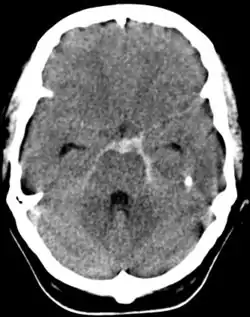

- Scanner cérébral en contraste spontané

Il est systématique et demandé en urgence : il permet de faire le diagnostic en décelant des hyperdensités au sein des espaces sous-arachnoïdiens (témoignant de la présence de sang frais) de topographie variable selon l'étiologie et la localisation d'une lésion éventuelle (vallée sylvienne, scissure inter-hémisphérique, citernes de la base, sillons de la convexité). La sensibilité est excellente dans les premiers jours[11]. Il recherche des complications (hématome cérébral, inondation ventriculaire, hydrocéphalie aiguë). Cette hyperdensité peut s'amoindrir, voire s'escamoter complètement après quelques jours d'évolution[5].